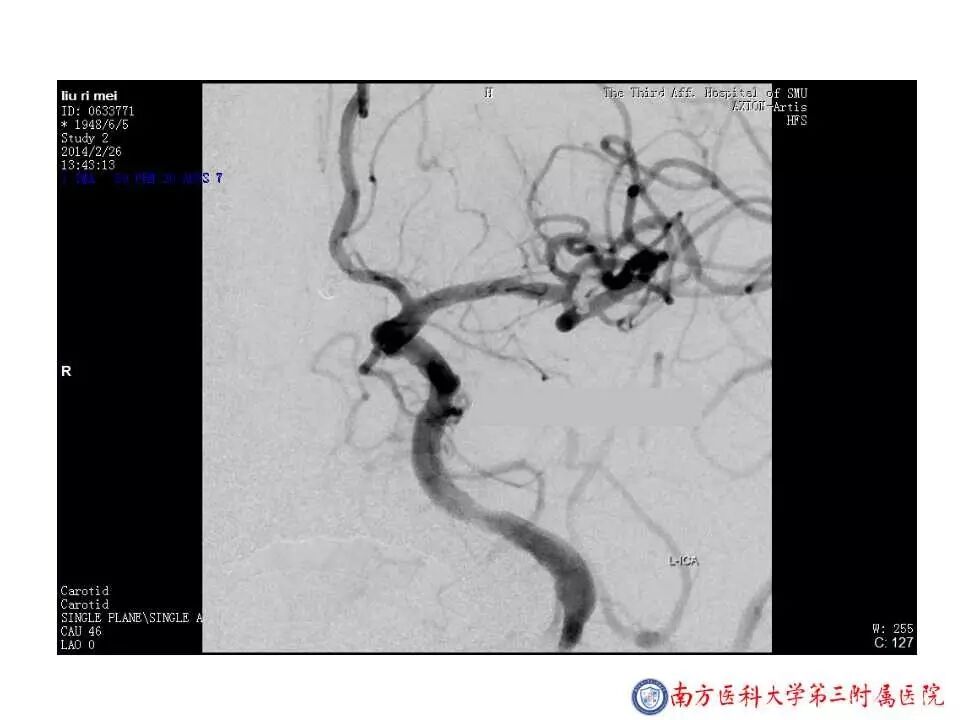

今天为大家分享的是“强生医疗CNV-神经介入专栏”第二十五期,由南方医科大学第三附属医院神经外科主任黄理金教授带来的“Enterprise支架辅助栓塞动脉瘤的优势”精彩讲课视频及PPT,欢迎观看。文章仅代表作者个人观点,如有不同见解,欢迎同道斧正!